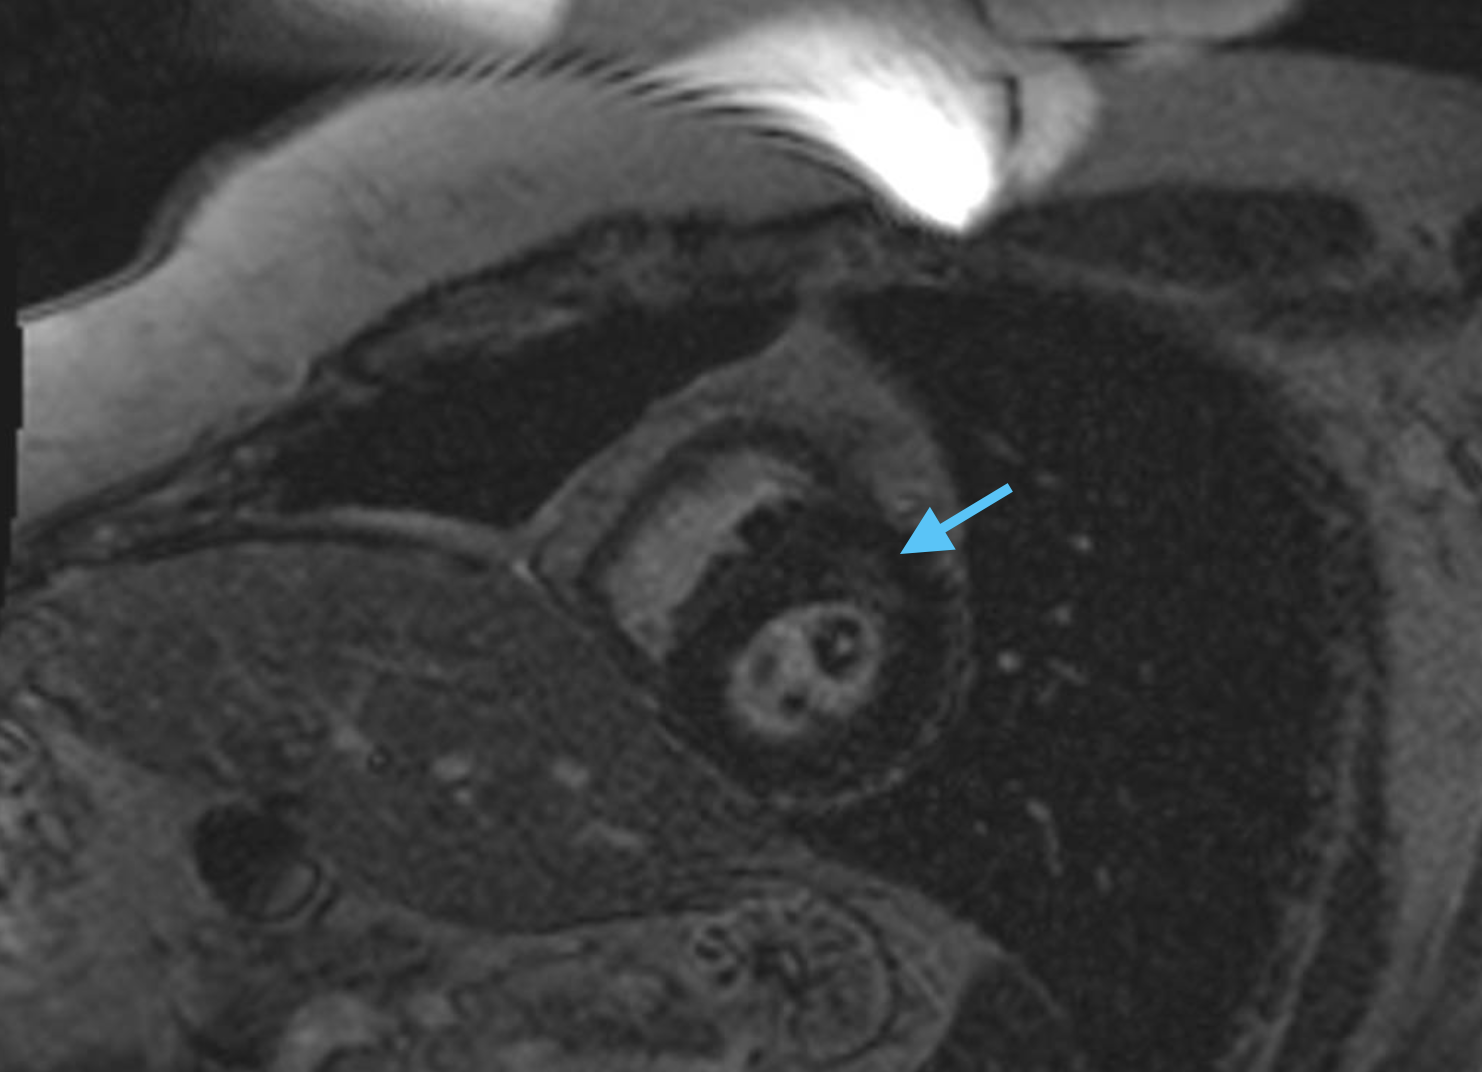

Figure 3: Representative CMR with patchy subendocardial LGE from cohort with variants of uncertain significance.